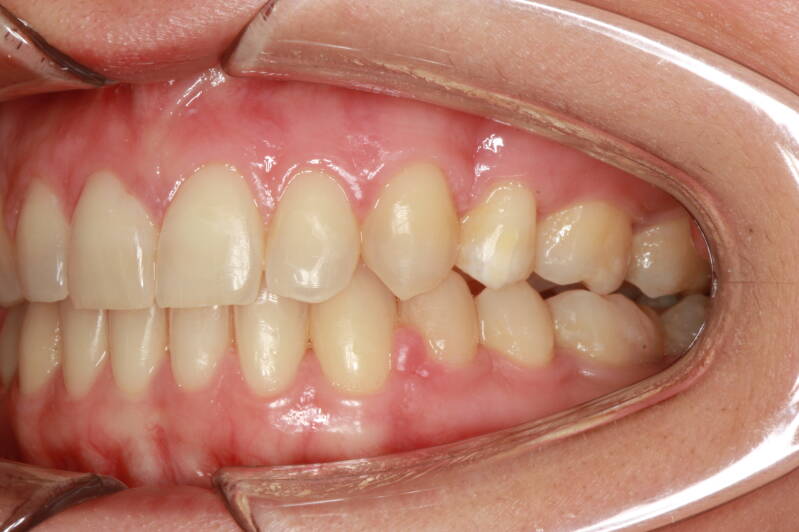

SECONDA CLASSE SUDDIVISIONE DESTRA

Questo mese vi presentiamo G.G. f. di15aa. Ha una seconda classe suddivisione destra molare e canina. richiesta Allineamento.

FOTO INIZIALI PRE TRATTAMENTO ORTODONTICO